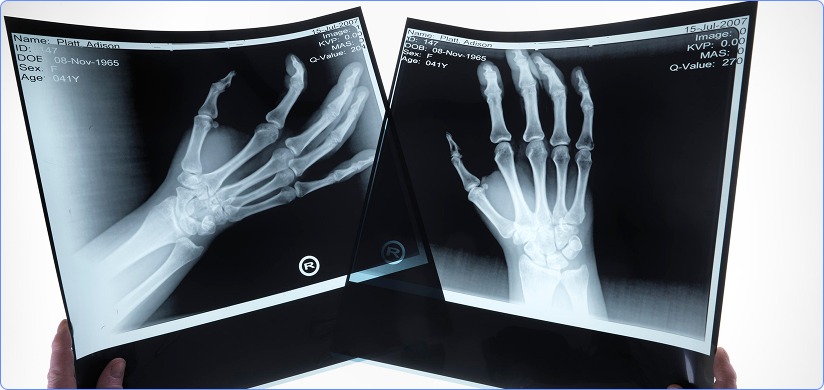

Upper Limbs X-Ray Reporting

Upper limb x-ray is a plain radiographic study which helps in the visualization of bone integrity, alignment, joint relationships, and indirect soft-tissues in the upper limbs area. These areas are generally affected by traumas and injuries. Dysfunctions in the upper limbs can be easily detected using x-ray. Upper limbs x-ray reporting consists of remote interpretation and reporting of upper limbs x-ray scans by subspecialty radiologists.